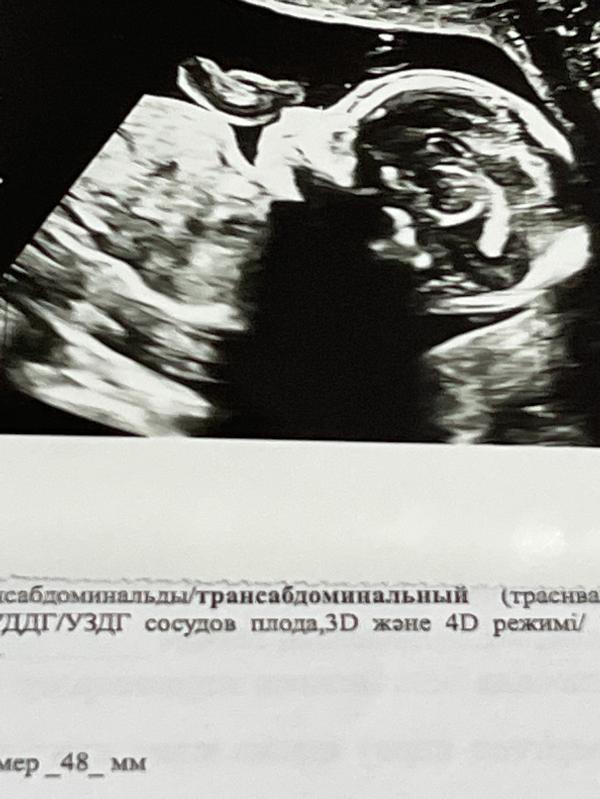

В моем случае Наследственности нет, в остальном все хорошо по узи, анализы сдавала после узи на 1 скрининге, не позвонили- думала хороший знак. На первом скрининге ставили аплазию, но исключили спустя неделю. Теперь вот длина 5.1мм при норме 5.5мм

Ставили тоже на 21 неделе, если честно по снимку узи он был даже короче вашего. Все хорошо, когда родилась дочка, сразу посмотрела на ее носик.